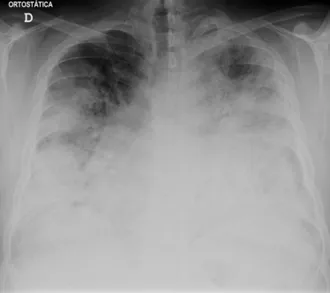

Legionärssjukdom är en allvarlig form av lunginflammation orsakad av Legionella-bakterier. Den sprids genom förorenad vattenånga eller fina vattendroppar som innehåller Legionella-bakterier. Legionella-bakterier trivs i varma, fuktiga eller stillastående vattenmiljöer, såsom luftkonditioneringsenheter, bubbelbad, rörsystem och stora vattensystem.

Personer som löper störst risk för legionärssjukdom inkluderar de över 50 år, rökare, före detta rökare och personer med lungsjukdomar eller nedsatt immunförsvar. Legionärssjukdom behandlas vanligtvis på sjukhus med antibiotika. Legionärssjukdom är ovanlig men kan vara allvarlig.